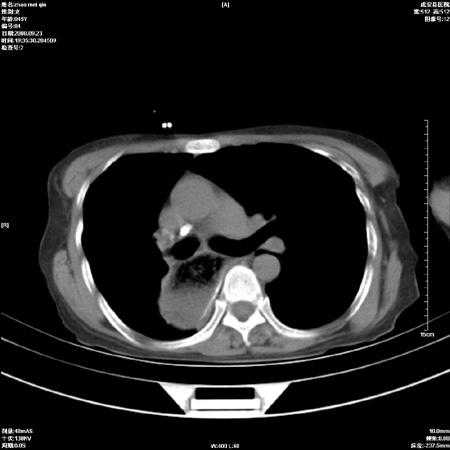

标题: CT15861:女 60 外伤后1小时 胸疼 [打印本页]

标题: CT15861:女 60 外伤后1小时 胸疼

外伤后1小时 胸疼 是外伤后引起的吗?

食道扩张明显下端逐渐变窄,倒像贲门失迟缓

食道ca术后胸腔胃,右肺挫伤?

考虑术后改变(胸腔胃),建议询问病史.

非外伤性改变,典型的贲门失迟缓症

食道扩张明显下端逐渐变窄,大量食物存留,象贲门失迟缓症。